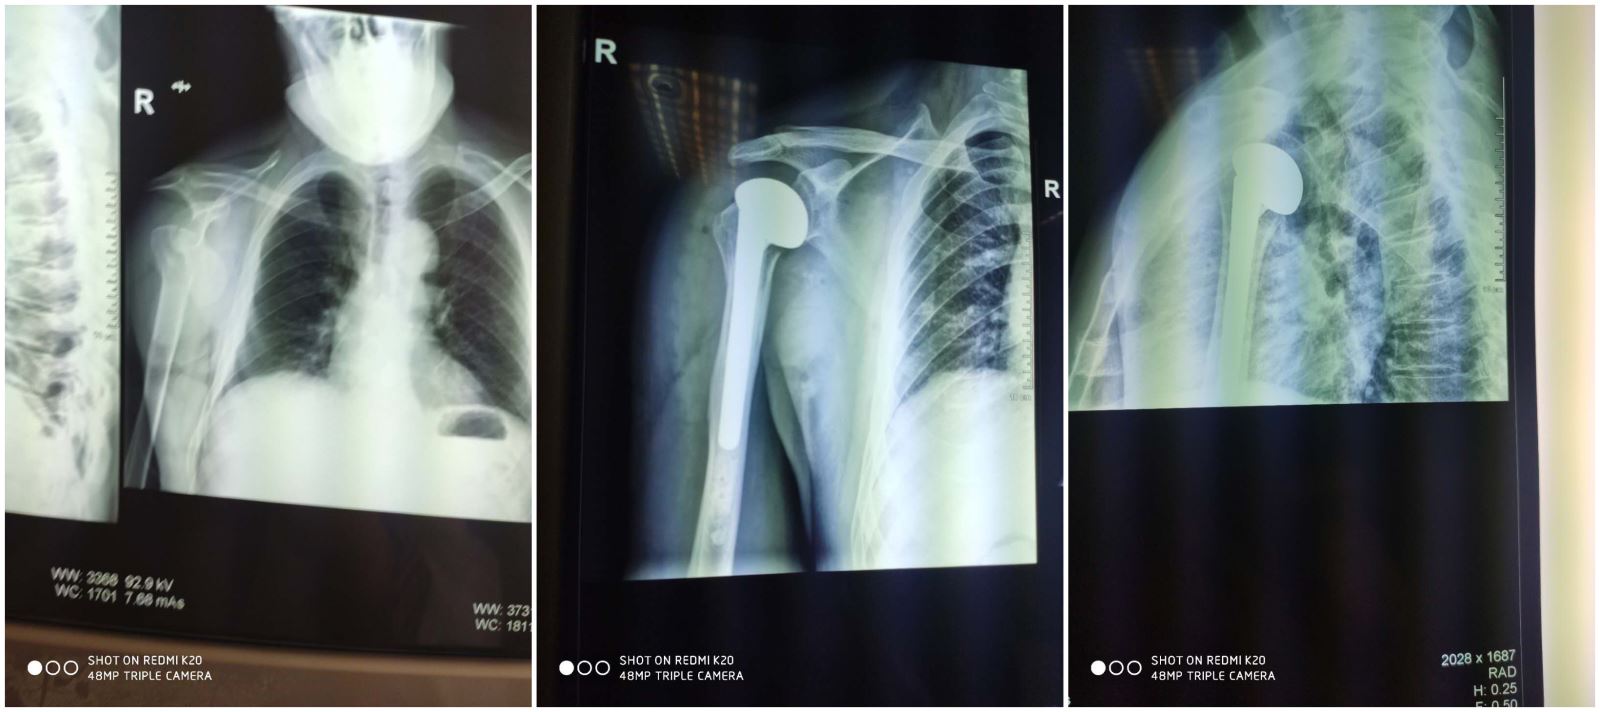

近日,我院骨三科完成一例右肩关节脱位伴肱骨头骨折人工肩关节置换术,此例手术的成功开展标志着我院骨三科人工关节置换水平迈上了新的台阶。

患者李某,男性,59岁,摔伤后右肩部剧烈疼痛,不能活动,急来我院就诊。检查发现患者伤势较重,经摄片诊断为“右肩关节脱位伴肱骨头骨折”,收治于我院骨三科。针对患者病情,兰荫梧主任组织科室骨干反复讨论。患者骨折移位较大,如行传统的“切开复位内固定术”治疗,复位困难,肱骨头后期坏死、不愈合的可能性较大,给骨折后期的功能康复带来巨大的隐患,影响患者日常生活,且需二次手术,加重患者负担,最适宜的治疗方法是实施人工肩关节置换手术。在与家属充分沟通后,骨三科医疗团队决定为患者施行右肩关节置换术。骨三科医疗团队积极完善术前检查,充分评估手术风险,拟定详细的手术方案、并发症应对措施以及规范的术后康复计划。手术由骨三科兰荫梧主任主刀、杨松涛医生协助。手术历时两个小时,完成顺利。患者置换后的肩关节对位良好,活动时的疼痛症状已经减轻,肩关节功能将获得最大限度的恢复。

据了解,肱骨近端骨折是肩关节创伤治疗的一大难题,由于肩关节功能要求较高、结构复杂,如果手术中对位不准或对位稍松、稍紧都会造成术后患者关节脱位或卡住,因而对手术者的技术水平要求很高。目前,人工髋、膝关节置换术已经在临床广泛应用,也为社会所理解和接受,但人工肩关节置换术开展却相对较晚,无论在实施数量及临床应用方面均不及人工髋、膝关节置换术,尤其在本地区开展更少。